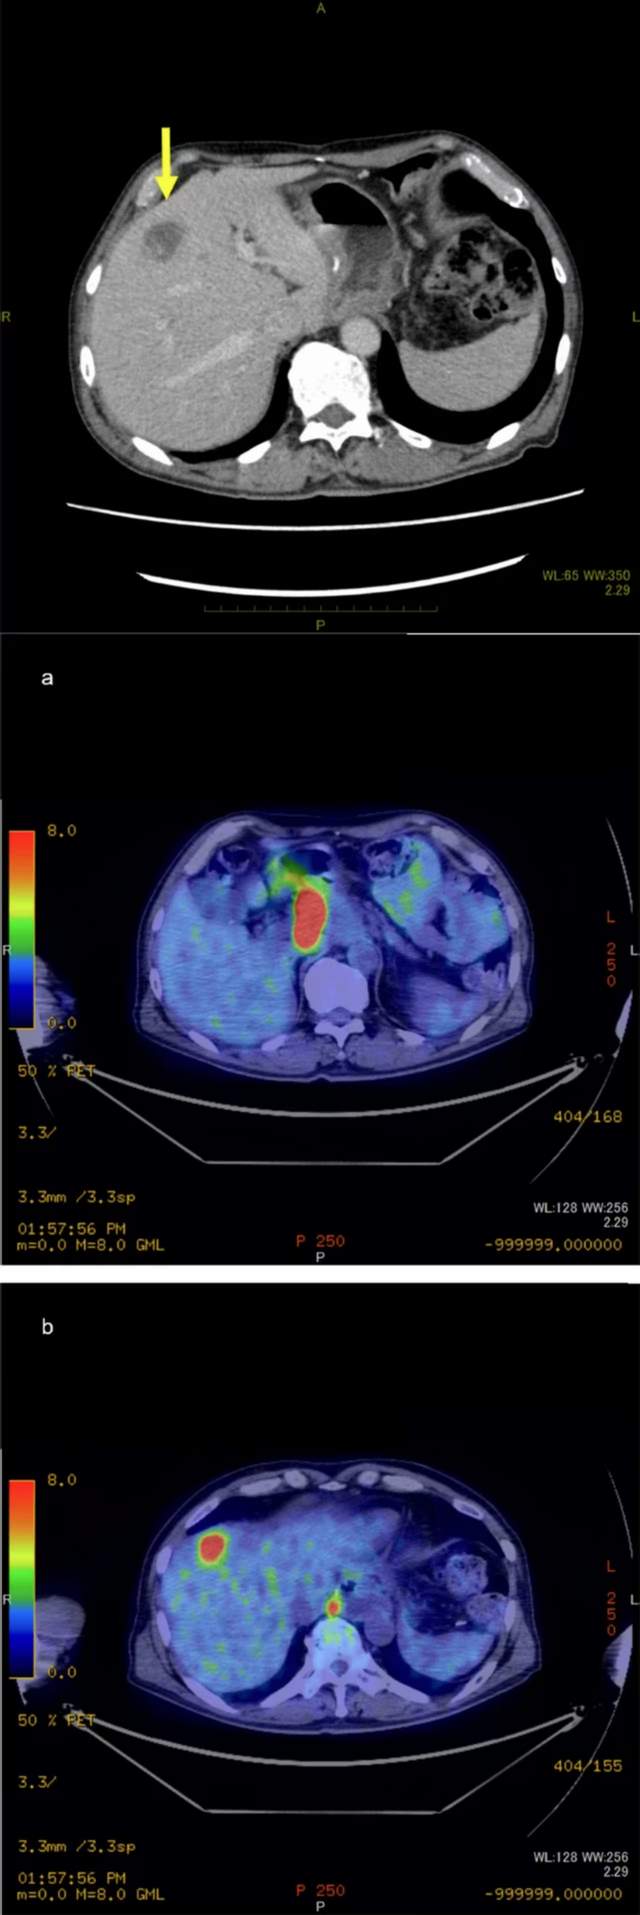

复发性食管癌患者实现5年长期生存

2022年,日本研究人员在《Journal of Medical Case Reports》发表了质子疗法实现复发性食管鳞状细胞癌患者长期生存的病例报告。该患者既往接受手术、化疗等治疗,但是最后发现癌症仍旧进展,并且观察到2个淋巴结转移以及一个大小21×15 mm的肝转移病灶。经过治疗后,患者已经实现持续完全缓解达到5年时间。